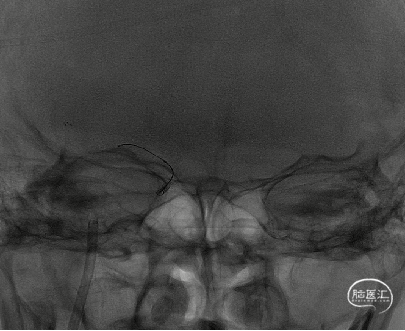

8F导引导管在多功能管及泥鳅导丝导引下直接进入右侧颈总动脉,此时Skathi远端通路导管尾端连接自制50ml负压注射器一路裸奔抽吸至C5段,反复抽吸3次,抽出大量血栓,回血通畅后,轻轻冒烟提示颈内动脉通畅,大脑中动脉M1远端闭塞,与取栓前后循环造影显示情况一致。

大脑中动脉M1段血栓采用SWIM技术-抽拉结合,避免血栓逃逸。

一次SWIM取栓,成功血管再通,达到mTICI分级:3级。